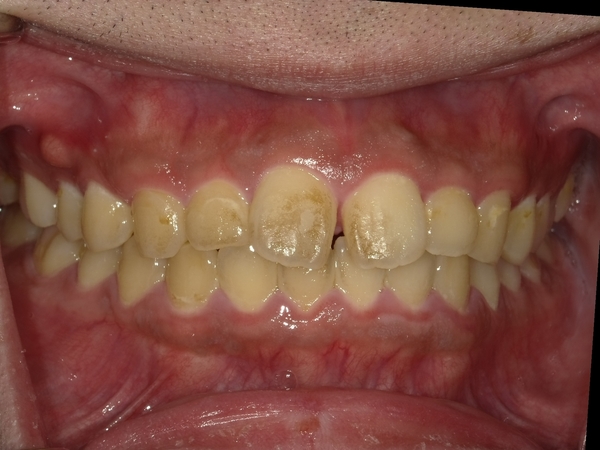

すきっぱ(空隙歯列)CASE7 2023.08.28 20代男性☆Before→After☆〇ご相談内容:前歯真ん中の隙間があいている〇矯正の種類:マウスピース型矯正「インビザラインGO」〇治療期間:19週間〇治療費用:44万円(税込) < すきっぱ(空隙歯列)CASE8すきっぱ(空隙歯列)CASE6 > ブログ記事一覧をみる